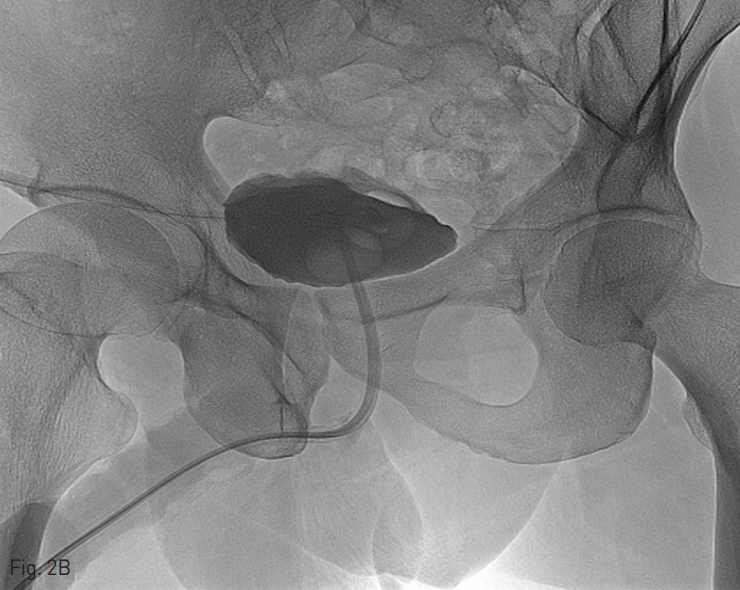

역행성 요로 조영술에서 bulbous urethral rupture 및 venous extravasation을 확인함.

Fig. 1

A retrograde urethrogram in a 48-year-old man shows complete anterior urethral disruption without filling of the proximal urethra and urinary bladder and demons trates venous extravasation. The 'Beak' (black arrow) of disrupted anterior urethra is shown.

먼저 생명을 위협하는 동반 손상을 치료한 다음, 손상된 요도의 위치 및 손상 정도를 먼저 파악하는 것이 요도 손상 치료의 첫 번째 단계이다. 역행성 요로 조영술이 가장 기본이 되는 검사이다. 본 증례에서도 일차적 중재 영상 의학적 요도 정렬술을 하기 전에 역행성 요로 조영술을 시행하여 손상 부위와 그 정도를 파악하였다. 특히 역행성 요로 조영술에서 손상된 요도 근위부가 새부리 모양을 보이면 설령 완전 요도 손상이라 하더라도 일차적 중재 영상 의학적 요도 정렬술을 성공적으로 시행할 수 있었다. Ali. 등에 의하면 컴퓨터 단층 촬영에서 비뇨 생식막이 뒤틀려 보이거나 좌골해면체근에 혈종이 있으면 요도 손상이 동반될 확률이 높다고 보고하였다.